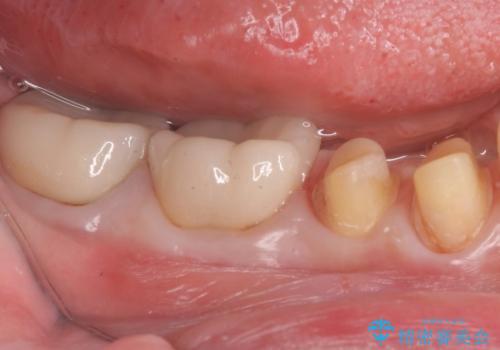

樹脂で継ぎ接ぎになった歯 セラミッククラウンでの治療

- 樹脂の材料の着色が気になるとのことで来院されました。

継ぎ接ぎになっている部分が多かったためクラウンでの治療となりました。

- 右下45:仮歯+ジルコニアクラウン/11,000円+110,000円費用は治療当時の料金となります

樹脂の材料と歯の境界部分は虫歯・着色の好発部位となります。

度重なる治療で継ぎ接ぎになってしまった場合はクラウンで歯を覆った方が虫歯・着色のリスクを減らすことができます。